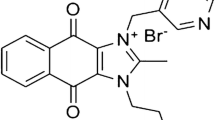

In order to coat the liposome structure with peptide, we conjugated DSPE-PEG-NHS to YSA. The molecular bonding took place between the NHS group of the DSPE-PEG-NHS and the a-amines of the YSA, as was assessed by Maldi-TOF mass spectrometry (Fig. 1). The conjugation efficiency was >98% (after purification unconjugated YSA 1187 Da was not detected). The narrow peak at 1187 Da (Fig. 1a) corresponds to YSA, the broad peak between 1500–2600 Da, centered at ~2000 Da (Fig. 1b) represented the DSPE-PEG-NHS compound, and the successful conjugation product)DSPE-PEG-YSA) is shown in Fig. 1c, with a mass of 2600–3400 Da. We then used the conjugated product for the preparation of YSA-L-DOX.